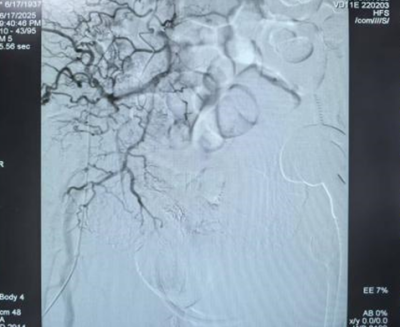

术前前列腺动脉明显增粗,紊乱

术后前列腺动脉栓塞良好